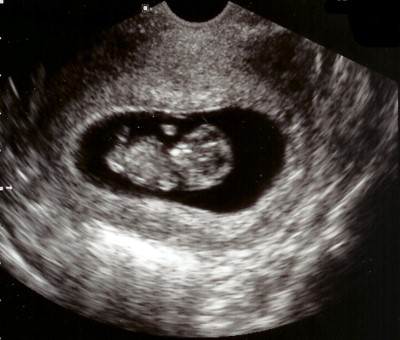

من أحد العلامات الأولى التي تشير إلى استقرار الوضع الصحي للجنين هو ظهور نبضه، فهو الذي يؤكد استمرار نمو الجنين بشكل صحيح. في الحقيقة، لا يوجد وقت محدد يشير عن بدء قلب الجنين بالنبض، وذلك لعدم معرفة اليوم المحدد الذي حدث فيه الإخصاب. لكن، يمكن للطبيب أن يعطي وقتاً تقريبياً لظهور النبض وهو من اليوم اثنين وثلاثين حتّى أربعةً وثلاثين يوماً من مرحلة الإخصاب وتلقيح البويضة. ويمكن للطبيب معرفة نبض الجنين عن طريق جهاز الموجات الصوتيّة، أو أجهزة الإشعاع الصوتيّة بعد مرور اثني عشر أسبوعاً على بدء الحمل.متى يبدأ تكوّن قلب الجنين

عادة يبدأ قلب الجنين بالتكوّن بعد الأسبوع الخامس من الحمل أي بعد مرور الشهر الأول، ويبلغ طول الجنين حوالي 1.25 مم، وتبدأ بعض الخلايا بالتشكيل. وفي نهاية الأسبوع الخامس، يبدأ الجنين يتخذ شكل معين ويبدأ الجزء العلوي من الدماغ بالبروز والظهور بشكل واضح. كذلك تقع حبة صغيرة في منتصف الجنين لتتطور وتصبح قلب الجنين فيما بعد. هنا يبدأ ظهور النبض، أي في الفترة ما بين الأسبوع السادس والأسبوع السابع من الحمل، ويمكن للطبيب معرفة ذلك عن طريق استخدام جهاز السونار فقط. ومع تقدم مراحل الحمل وتطوره، يمكن للطبيب سماع نبض الجنين بالسماعة الخاصة به، أي بعد مرور الاسبوع العشرين من الحمل.متى يظهر النبض عند الجنين

يبدأ نبض الجنين في عمر ما بين خمسة وستة أسابيع، ويقصد به أنه يمكن مشاهدته عن طريق السونار أي التصوير التلفزيوني.